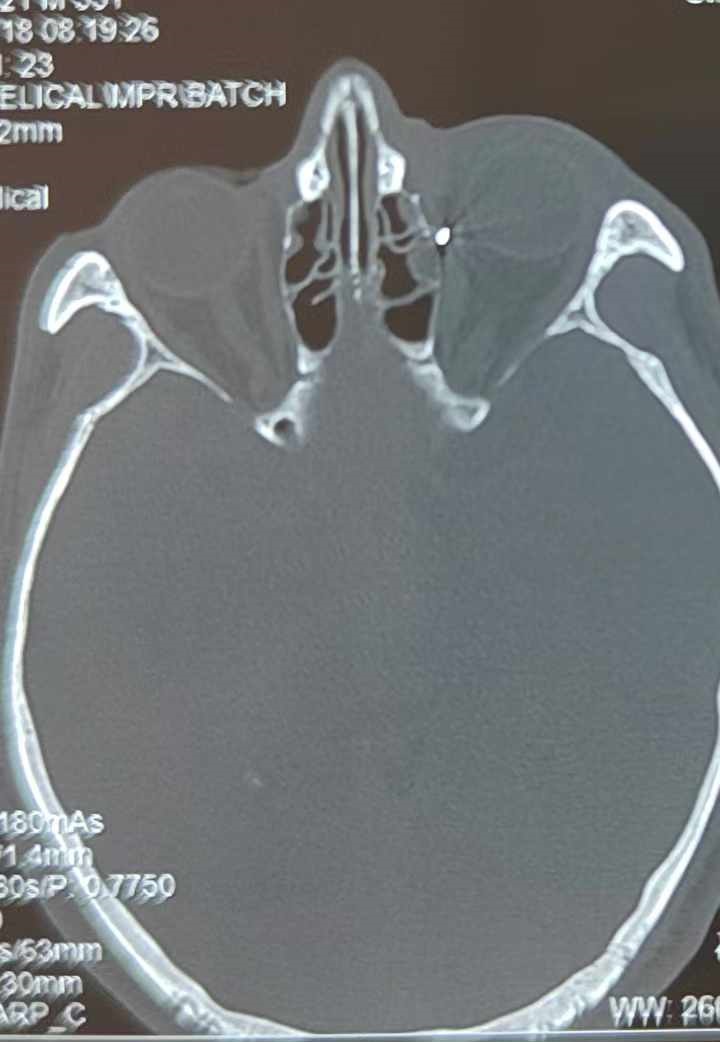

從CT報(bào)告中可以看出,高先生眼內(nèi)的異物不是很大,但位于眼窩深處,緊鄰鼻骨,從CT影像判斷應(yīng)該是金屬或合金異物。一般臨床上遇到這樣的情況,醫(yī)生會(huì)建議“保守觀察”,若異物傷及神經(jīng)、發(fā)生炎癥感染等,則需到條件較好、有眼眶病和眼外傷專業(yè)醫(yī)師的醫(yī)院進(jìn)行二期眶內(nèi)異物取出術(shù)(2021年《中國眼眶異物診斷和治療專家共識(shí)》)。

李海波博士介紹,眶內(nèi)異物想要通過手術(shù)取出,難度很大,一是因?yàn)槲恢秒[匿,無法實(shí)現(xiàn)可視化操作;二是如果是磁性異物,現(xiàn)有手術(shù)工具磁性強(qiáng)度有限,很難吸出這么深的異物;三是可操作空間極為狹小,眶周軟組織多,異物周邊包裹緊密,像高先生這種情況,異物周邊還有很多神經(jīng)、血管,手術(shù)難度更高。